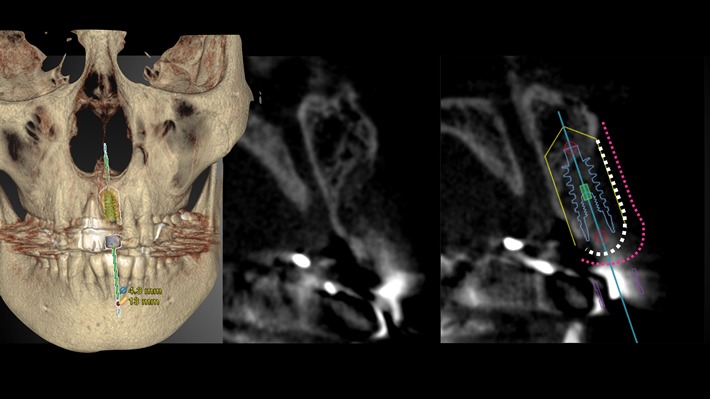

Nobel Clinician による埋入位置、埋入角度のシミュレーション